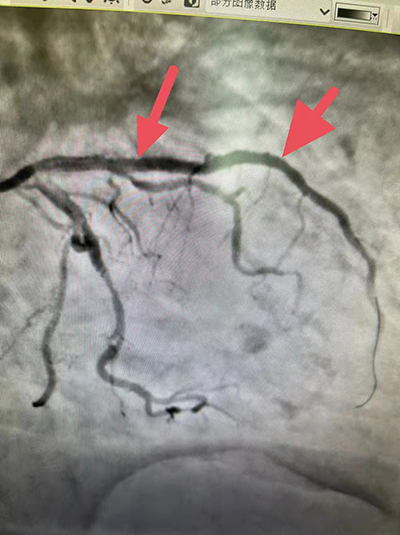

术前冠脉造影:前降支完全闭塞!右冠脉也有多处狭窄。

造影诊断:多支血管病变,前降支近端100%血栓闭塞。